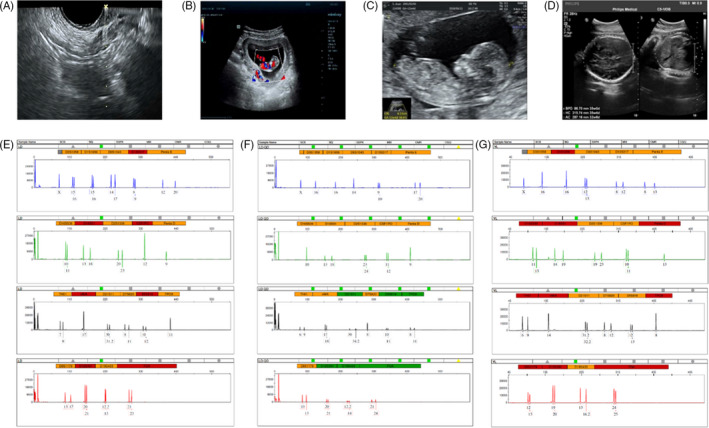

收集了15名接受取卵的患者的基本特征,包括取卵周期、胚胎移植和妊娠次數。一般來說,四個胎兒沒有出生缺陷,三個胚胎來自ICSI的受精類型,而最后一個是自然受孕的。1例術中超聲掃描顯示,在經陰道超聲(TVUS)引導下,卵巢未見間質增生或其他異常卵巢結構(圖2A)。這名婦女在體外受精后成功懷孕,并在第8周進行了基本產前程序的超聲掃描(圖2B),第13周(圖2C) 和第32周 (圖二維) 顯示正常的胎兒發育。微衛星位點分析顯示,胎兒(圖2F)與母親有遺傳關系(圖2E) 供體UCMSC以外的其他人(圖2G)。

圖2:妊娠和新生兒結局。(A)超聲掃描顯示USMSCs移植過程中有穿刺過程;(B-D) 孕周 8 周 (B)、13 周 (C) 和 32 周 (D) 妊娠患者的超聲檢查;(E-F) 母血(E)、胎兒臍帶(F)和供體細胞(UCMSCs)(G)的微衛星位點分析